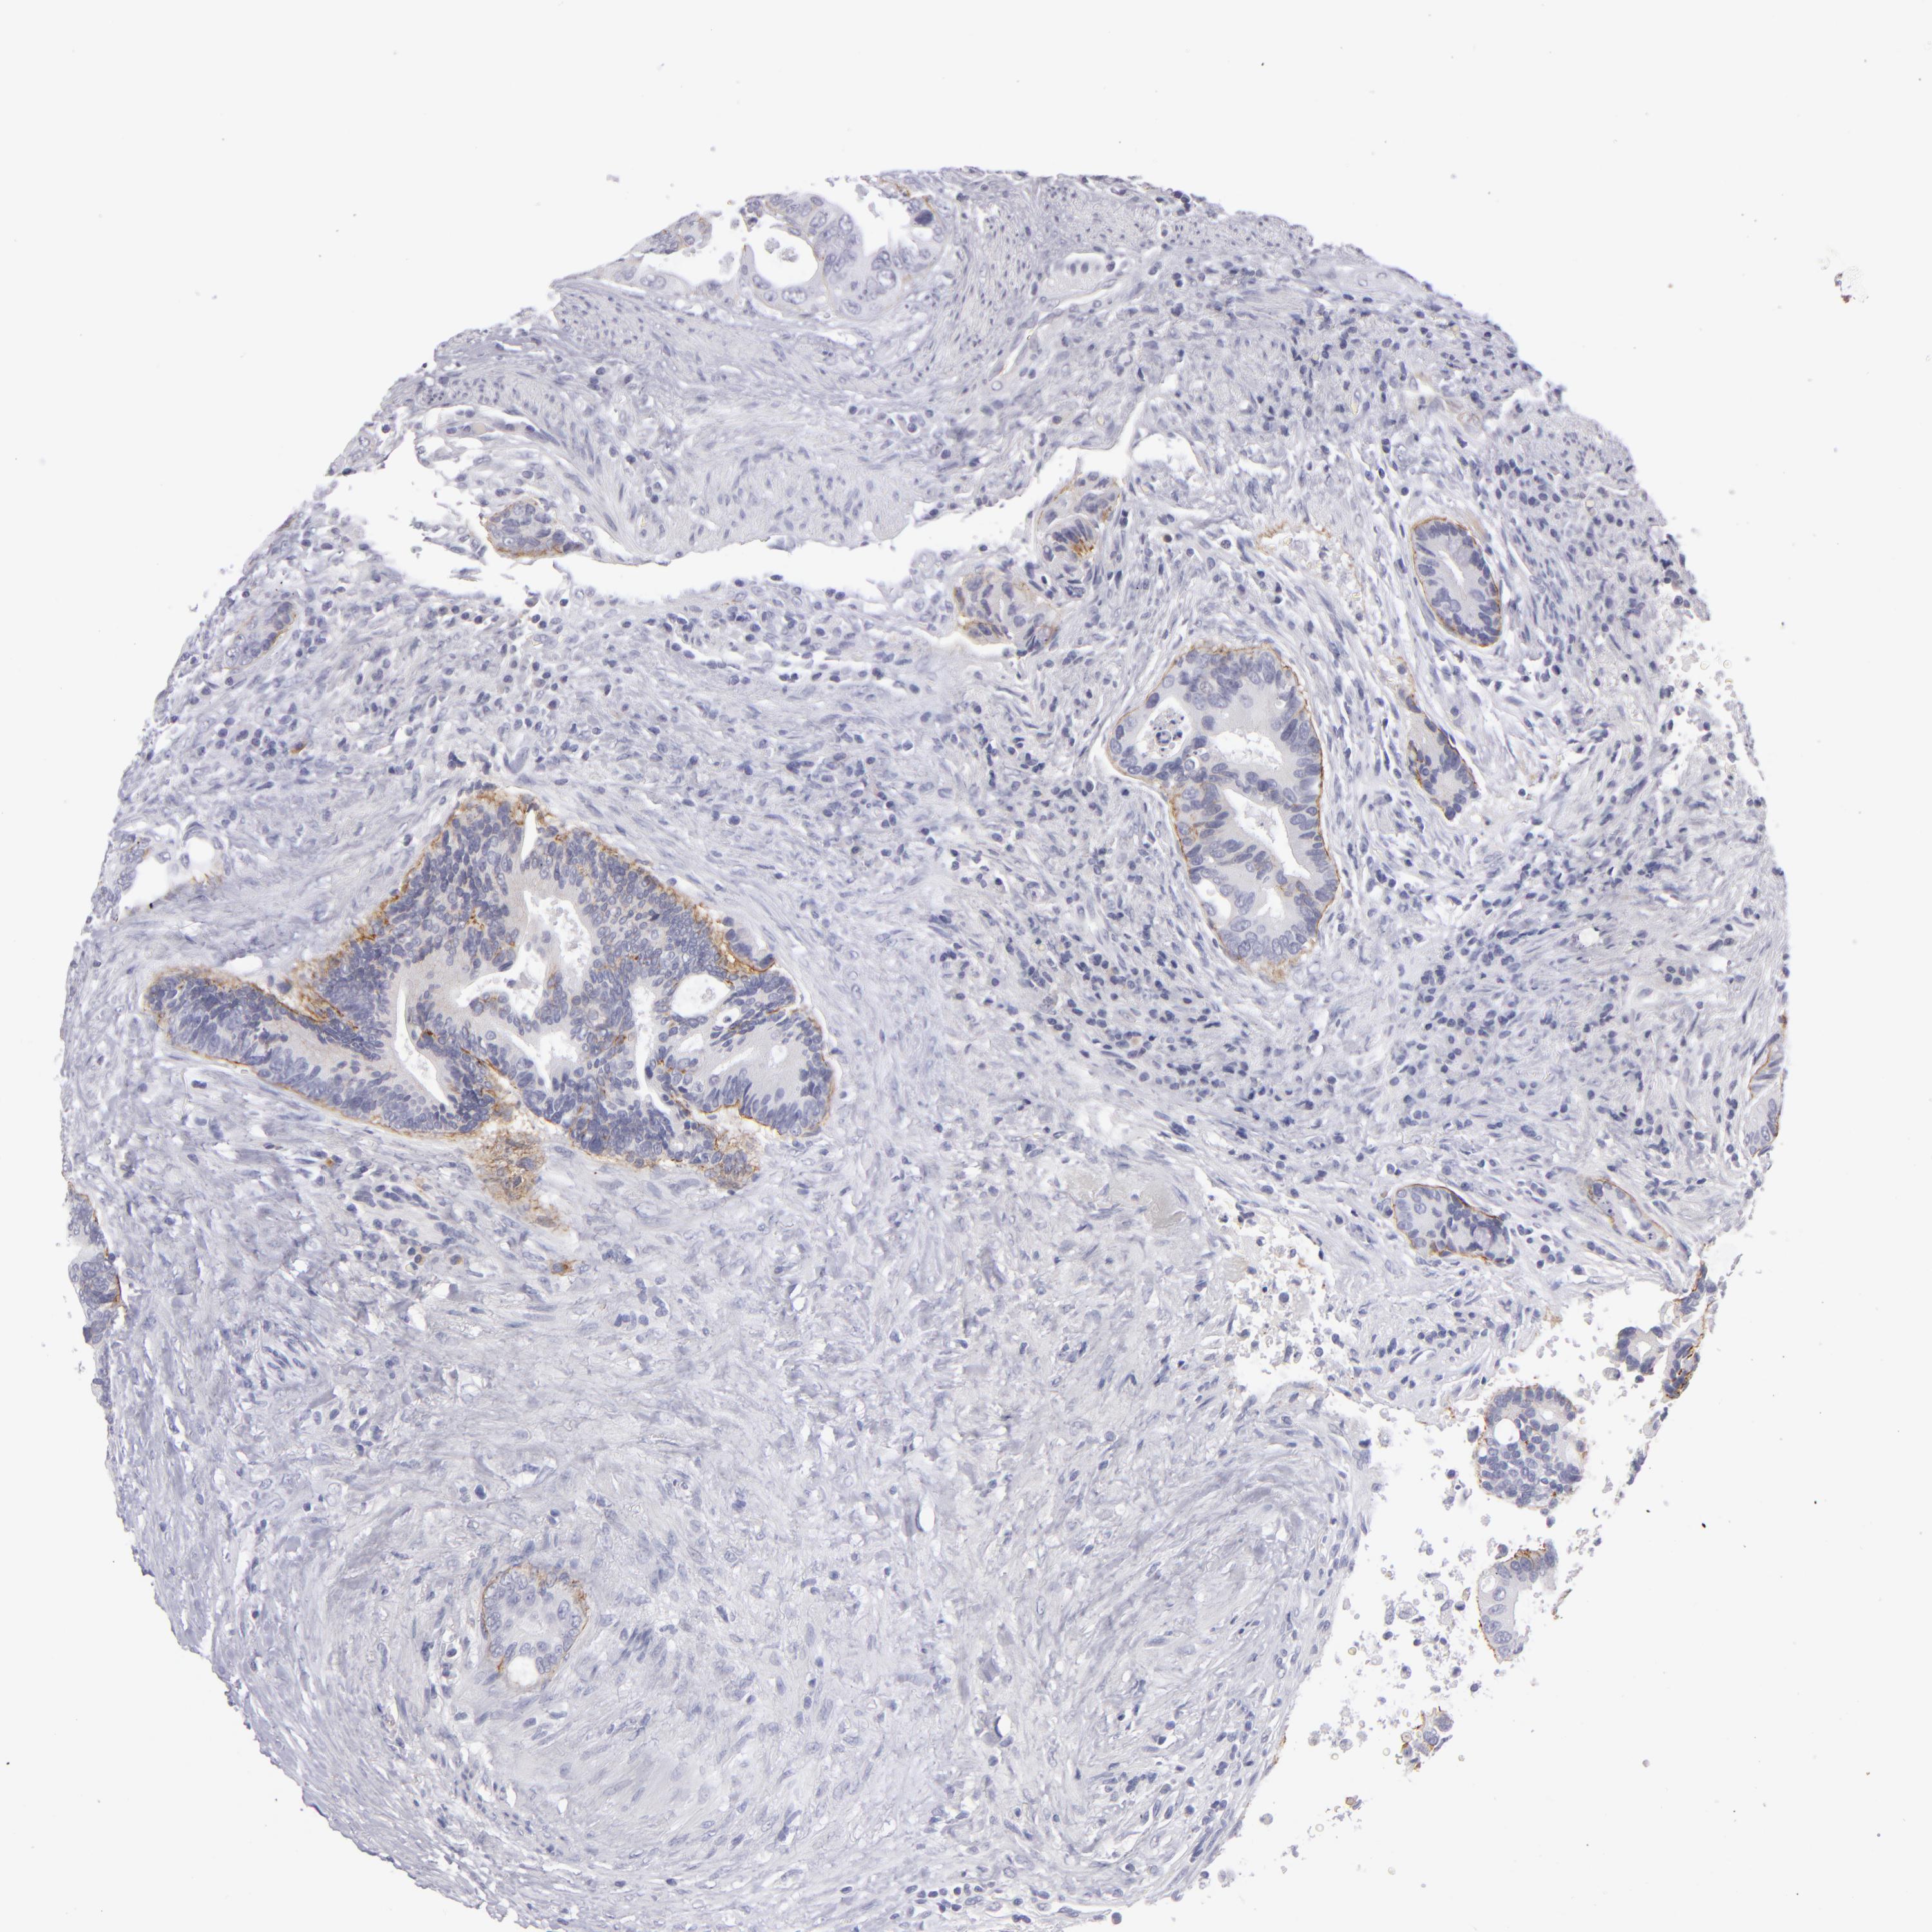

CANCER COLORECTAL CANCER Show tissue menu

Colorectal cancer

Human cancer

Colon adenocarcinoma